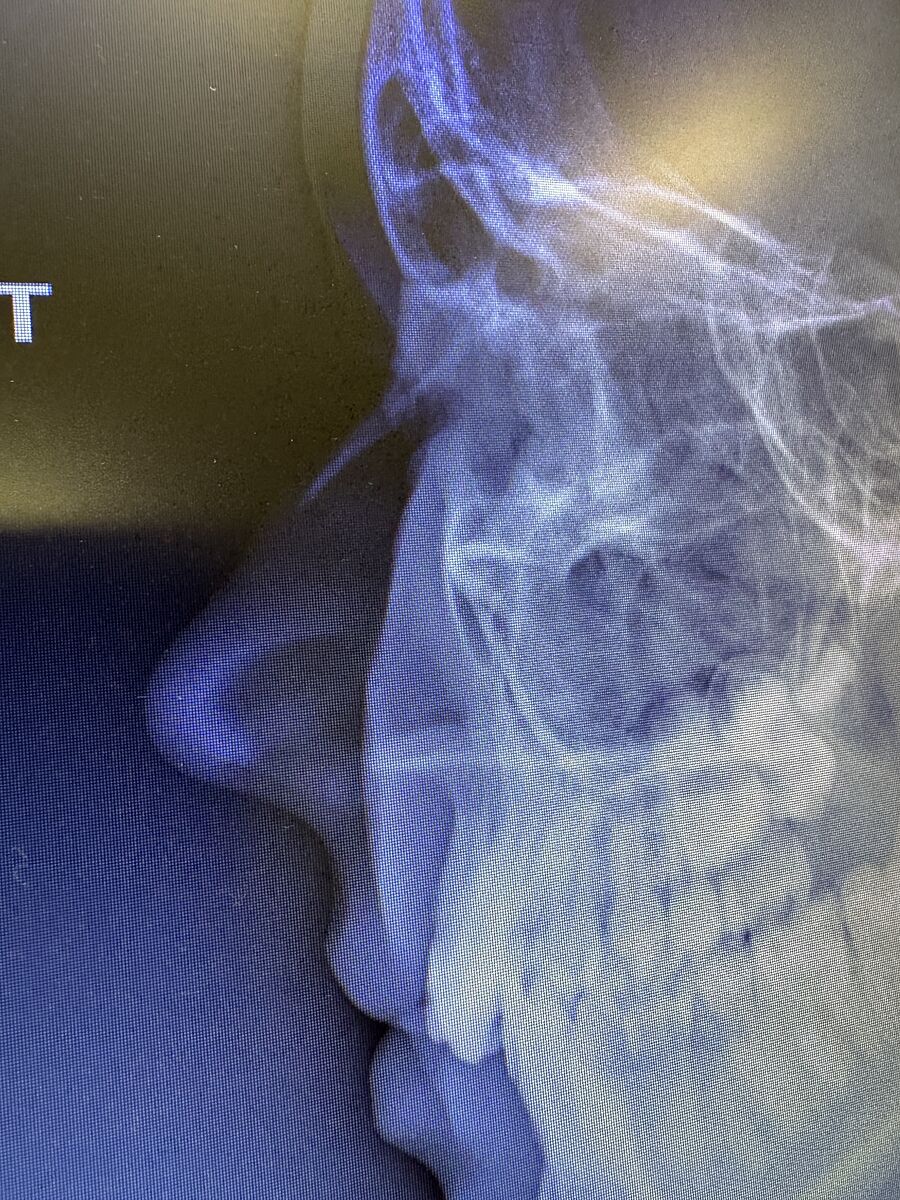

Дівчата,підкажіть будь ласка чи видно в цій проекції,що в дитини немає перелому та тріщин носа,хто компетентний,будь ласка,чи ще треба робити прямо проекцію рентген,чи цього достатньо?Дякую!!!